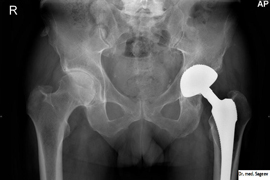

Гормонозаместительная терапия после эндопротезирования тазобедренного или коленного суставов снижает риск повторной операции на 40%-50%. Об этом свидетельствуют результаты исследования, опубликованные в журнале Annals of the Rheumatic Diseases.

Авторы работы изучили медицинские данные 10,8 тыс. женщин, прошедших процедуру эндопротезирования коленного или тазобедренного суставов в 1986-2006 годах. Из них 8100 женщин не проходили гормонозаместетельной терапии, тогда как 2700 пациенток принимали соответствующие препараты по меньшей мере шесть месяцев. Риск повторного протезирования в обеих группах отслеживался в течение минимум трех лет.

Проанализировав полученные данные, ученые отметили, что прием гормональных препаратов в течение шести месяцев после операции на 38% снижает вероятность повторного эндопротезирования. При этом годовая терапия позволяет сократить риск на 50%. Однако, обращают внимание исследователи, дооперационная гормонозаместительная терапия не влияет на успешность приживления имплантата. Стоит отметить, что после учета таких факторов, как прием лекарств, препятствующих обновлению костной ткани, результаты исследования не изменились.

Известно, что низкий уровень эстрогена ускоряет истончение и разрушение костной ткани. Правильно подобранная гормонозаместительная терапия препятствует этому процессу. Тем не менее, необходимо проведение дополнительных исследований, доказывающих эффективность применения такого лечения после эндопротезирования суставов.

По данным британского минздрава, приблизительно 2% пациентов в течение трех лет требуется повторная операция по эндопротезированию сустава, причем в 75% случая из-за остеолиза - полного рассасывания всех элементов костной ткани.